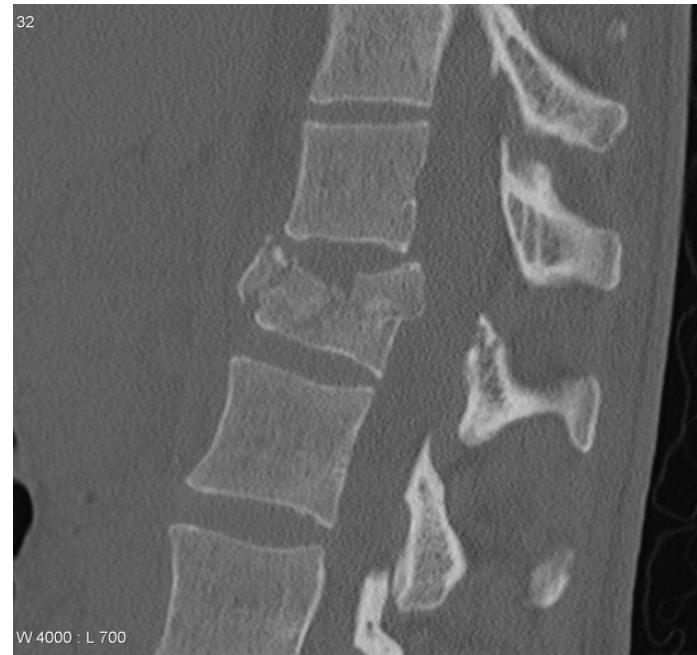

Thoracolumbar Burst Fractures

- Mechanism: High-energy traumatic vertebral fractures caused by flexion of the spine leading to compression force through the anterior and middle column

- Pathology: Retropulsion of bone into the spinal canal and compression of neural elements

- Gold standard investigation: CT scan

- Treatment: Bracing or surgical decompression and stabilization depending on neurologic deficits and instability risk